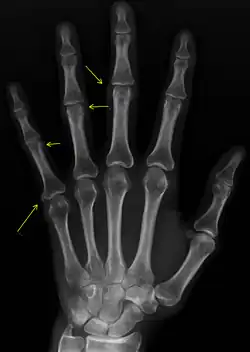

X-rays showing calcinosis in a woman with CREST syndrome

X-ray of subtle calcifications in CREST syndrome

Calcinosis

CREST causes thickening and tightening of the skin with deposition of calcific nodules ("calcinosis").